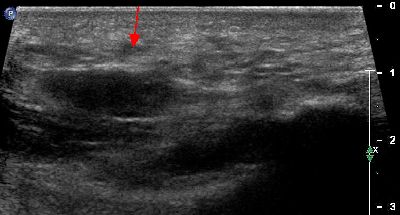

Tendinopatia achillea Lesione tendine d'Achille 01